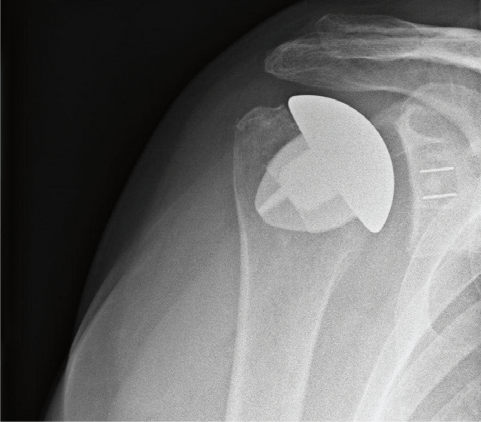

Schaftfreie Schulterendoprothese (Humeruskopfersatz)

Wann immer möglich wird ein sog. Humeruskopfersatz verwendet. Diese schaftfreie Schulterendoprothese erlaubt einen sehr knochensparenden Ersatz des Schultergelenkes und ermöglicht auch einen Austausch der Gelenkpfanne, falls diese sich im Laufe der Jahre auch abnutzt. Vorraussetzung für den alleinigen Ersatz der Kopfes ist eine ausreichend gute Knorpelschicht auf der Pfanne. Sollte irgendwann einmal eine Wechseloperation notwendig sein, bleiben durch die knochensparende Implantation alle Möglichkeiten für einen Wechsel der Prothese erhalten. Das Fallbeispiel zeigt eine Nekrose (Abgestorbener Knochen) eines großen Teils des Oberarmkopfes. Das Bild mit eingebrachter Kopf-Prothese den Zustand 5 Jahre nach der Operation.